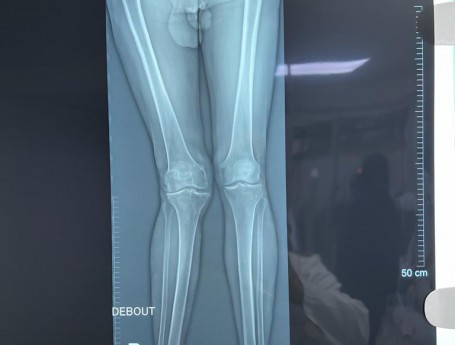

Total Knee Arthroplasty on a severe Genu Valgum

• Total Knee Arthroplasty on a severe Genu Valgum